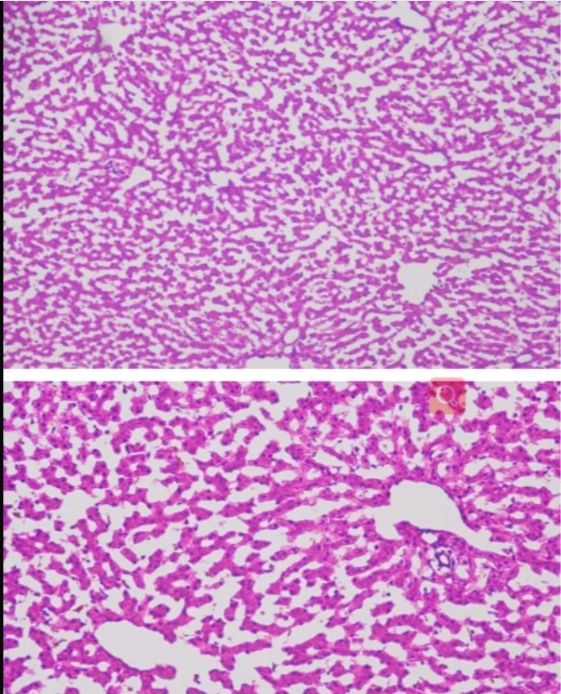

→根據顯微鏡下的觀察,鑒別切片中的組織類型和細胞形態。不同的組織類型和細胞形態反映了不同的生理或病理狀態。

→注意觀察細胞的大小、形狀、排列方式以及細胞核和細胞質的特征,這些特征可以提供關于細胞狀態的重要線索。

→觀察細胞是否出現異常增大或縮小,核的大小、形狀、染色深淺等是否正常,以及細胞質的染色情況是否有顆粒感、空泡等異常改變。

→分析細胞分裂相的數量,判斷細胞的增殖活性。觀察組織的排列是否整齊,有無紊亂現象;組織間隙是否清晰,有無水腫、炎癥等改變。

→根據血管的形態、數量、走行等判斷血管狀態。觀察炎癥細胞的種類、數量、分布等,判斷炎癥的性質和程度。